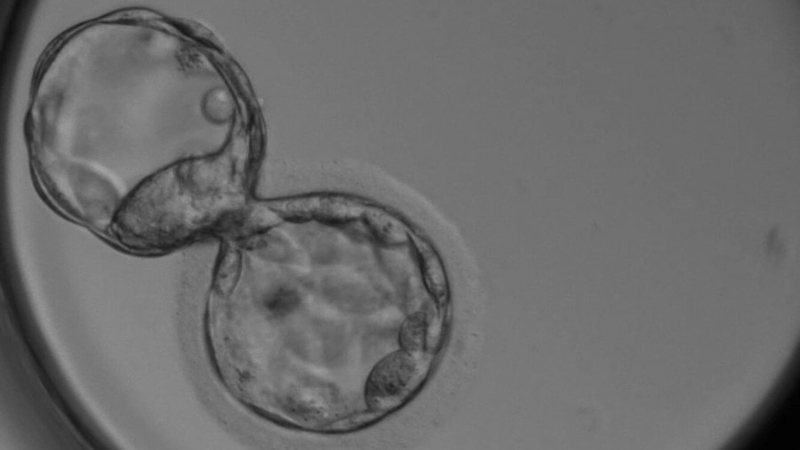

Sinh thiết phôi là một kỹ thuật y học còn có tên gọi khác là kỹ thuật xét nghiệm di truyền tiền làm tổ (Preimplantation genetic testing – PGT) được áp dụng để xác định các vấn đề di truyền trong phôi sản xuất từ quá trình thụ tinh ống nghiệm (IVF). Việc kiểm tra di truyền tại giai đoạn này, trước khi phôi được cấy vào tử cung, nhằm đảm bảo việc lựa chọn phôi khỏe mạnh nhất cho việc cấy ghép. Dưới đây là một số lợi ích chính của PGT (sinh thiết phôi):

Để thực hiện xét nghiệm di truyền tiền làm tổ, bước đầu tiên cần thực hiện là quá trình thụ tinh ống nghiệm, trong đó trứng sẽ được lấy ra và thụ tinh cùng tinh trùng trong môi trường ống nghiệm. Sau đó, phôi sẽ được nuôi dưỡng và chăm sóc trong tủ cấy cho đến ngày thứ 5.

Tiếp đến, bác sĩ sẽ thực hiện việc lấy mẫu từ phôi ở ngày thứ 5, cụ thể là lấy khoảng 3 – 5 tế bào từ phôi. Do phôi 5 ngày tuổi đã có hơn 150 tế bào nên việc này không ảnh hưởng tới chất lượng của phôi.